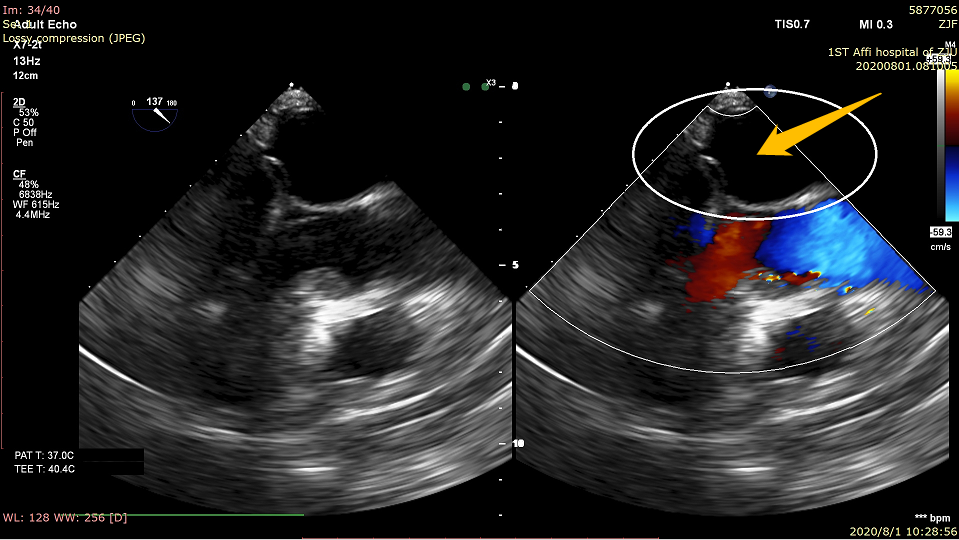

该例患者为73岁男性患者,主因“活动后气促十余年,加重二十余天”入院,诊断为重度二尖瓣关闭不全。患者的超声心动图提示二尖瓣后叶脱垂、腱索断裂并伴有重度二尖瓣反流(4+)。经过多学科团队的全面评估和反复讨论论证,马量主任、李伟栋主任及其团队认为该患者外科开胸心脏手术风险大,经心尖MitralStitch®微创二尖瓣修复手术是该患者的最佳治疗方式。手术在患者全麻状态下进行,术中于患者肋间行3-4cm小切口,经心尖穿刺送入器械,于二尖瓣A2区和P2区分别植入人工腱索完成缘对缘修复,并于P1区完成人工腱索植入,术后即刻二尖瓣反流量由重度(4+)变为无反流(0),二尖瓣瓣膜功能即刻恢复正常。手术操作在单纯超声引导下进行,手术过程平稳顺利,仅耗时25分钟。患者术后康复顺利,第2天便可自己下床活动,出院前复查超声心动图显示二尖瓣反流量为(0+),手术效果极佳。此次手术的成功标志着MitralStitch®确证性临床研究在浙大一院正式开展。

术后:0反流